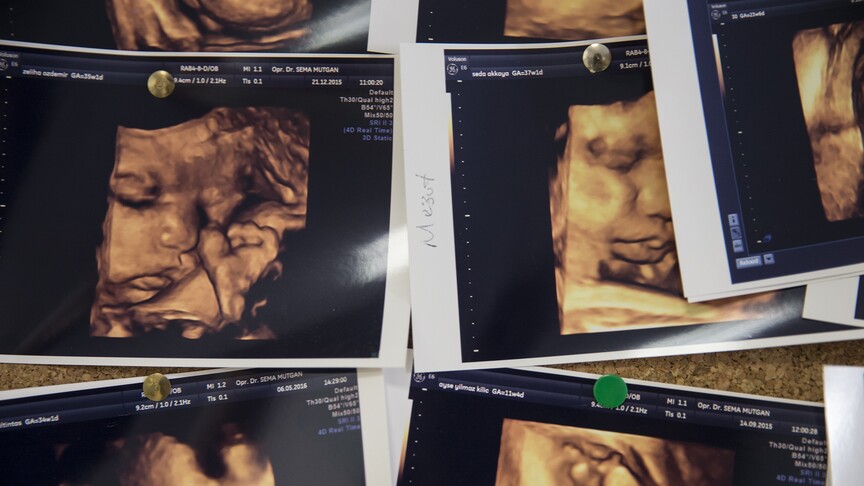

Uzman Uyardı: Annenin Gençliğindeki Mutasyon Bebeğinde Hemofiliye Neden Olabiliyor

Hemofili hastalığının erken tanısı ve aile içi geçiş mekanizmaları, Antalya’da düzenlenen 23. Türkiye Hemofili Kongresi’nde ele alındı. Uzmanlar, yenidoğan erkek çocuklarda aile öyküsü varsa mutlaka tahlil yapılması gerektiğini vurguladı.